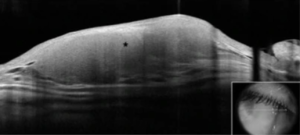

The primary presenting sign of benign CRLH is often a slow growth tumor in the conjunctiva in the form of a salmon-colored lesion, with little conjunctival infection and no significant neovascularization upon slit-lamp examination (Fig. 1).[7]